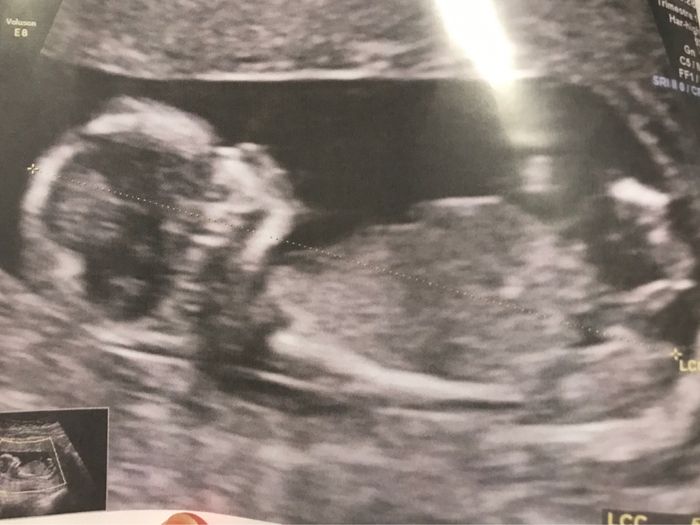

Notre petit bout est né l'année dernière le 5 juin il a donc fait 1 an par chance ayant repousser le mariage il pourra participer il faut toujours voir le bon coter des choses ! Donc il amènera les alliances ! Il commence à marcher mais n'est pas...